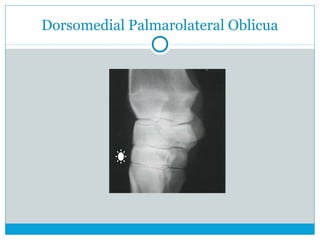

Dorsomedial Palmarolateral Oblicua

 Dorsomedial Palmarolateral Oblicua